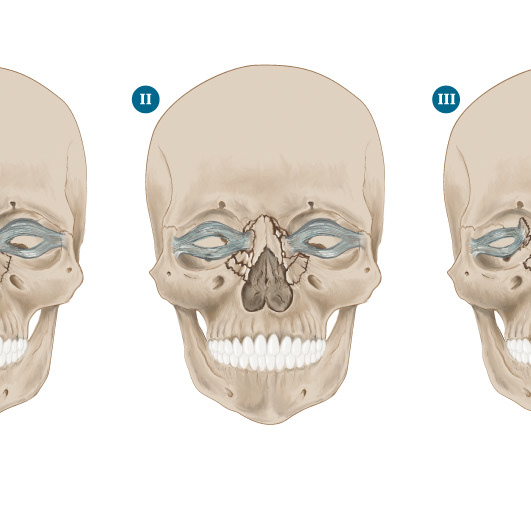

Proceso / Maxilofacial